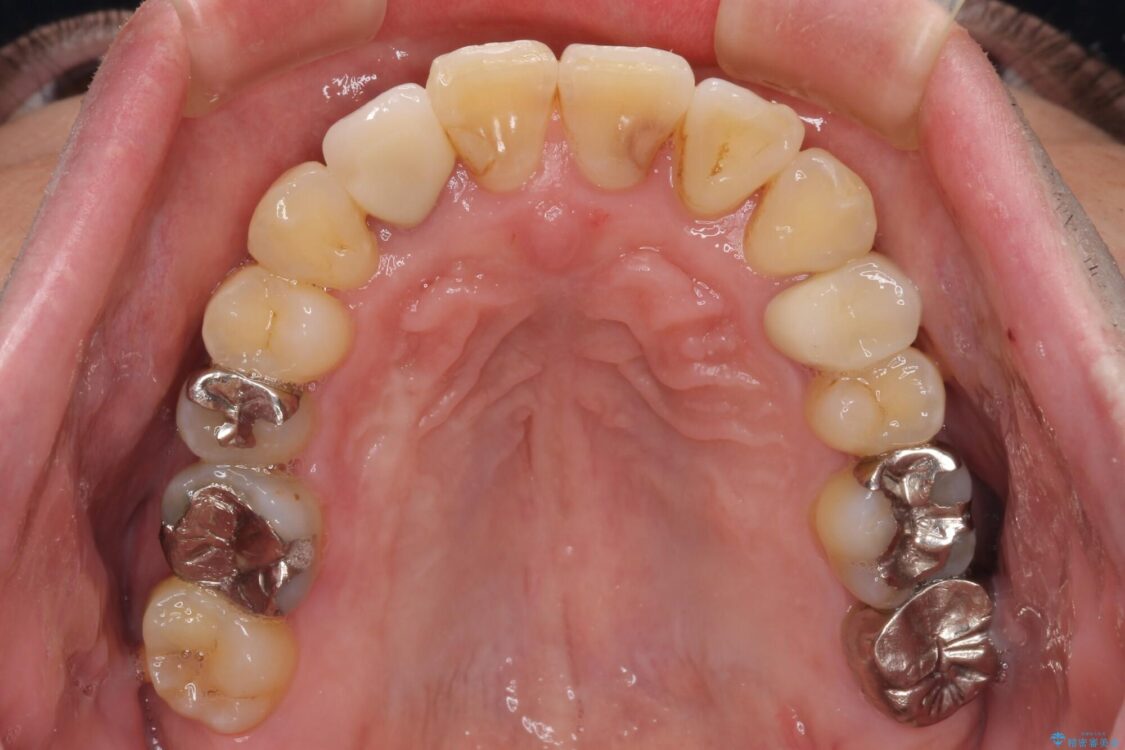

奥歯の痛みと前歯のデコボコを気にして来院された患者様です。

左右下顎の大臼歯は、ともに歯根が破折しており、抜歯が必要な状態でした。

放置したことで炎症による骨吸収が顕著であるため、骨造成を併用してインプラント埋入を行うこととしました。

咬み合わせは受け口傾向であり、上顎前歯の叢生が顕著であったことから、第1小臼歯抜歯による矯正治療も検討しましたが、下顎大臼歯を左右ともに抜歯するため、非抜歯による矯正治療を行うこととしました。

治療前